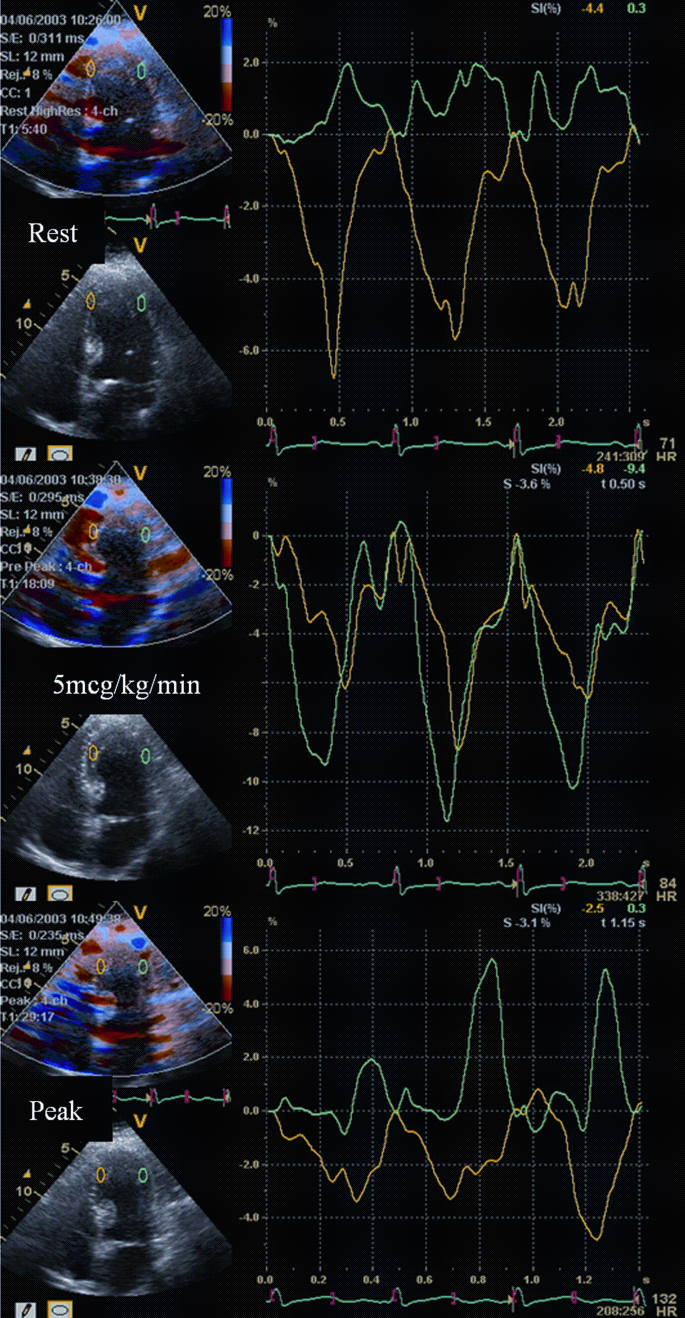

» Interpreting stress echo (99) 사진

Interpreting stress echo (99) 사진